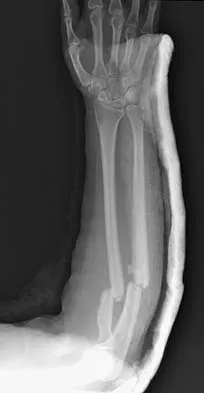

A 32-year-old woman sustained an injury to her left upper extremity in a motor vehicle accident. Examination reveals a 2-cm wound in the mid portion of the dorsal surface of the upper arm and deformities at the elbow and forearm; there are no other injuries. Her vital signs are stable, and she has a base deficit of minus 1 and a lactate level of less than 2. Radiographs are shown in Figures 9a and 9b. In addition to urgent debridement of the humeral shaft fracture, management should include

Explanation

With a severe injury to the upper extremity, the best opportunity for achieving a good functional result for a floating elbow is immediate debridement of the open fracture, followed by internal fixation of the fractures. The ability to do this depends on the patient's physiologic status. In this patient, the procedure is acceptable because she has normal vital signs and no chest or abdominal injuries, and normal physiologic parameters (base excess and lactate) show adequate peripheral perfusion. The surgical approaches will be determined by the associated injury patterns and open wounds. In this patient, the humerus was debrided and stabilized through a posterior approach as was the medial condyle fracture. The ulna was fixed through an extension of the posterior incision and the radius through a separate dorsal approach. Solomon HB, Zadnik M, Eglseder WA: A review of outcomes in 18 patients with floating elbow. J Orthop Trauma 2003;17:563-570.